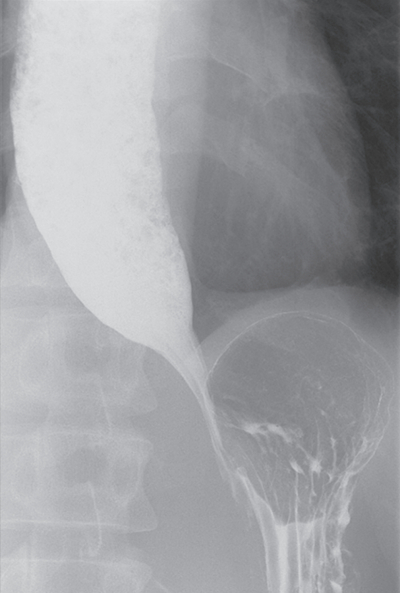

40歳の女性。嚥下困難と嘔吐とを主訴に来院した。35歳を過ぎたころから前胸部に食物のつかえを感じるようになった。1年前から食物がつかえたときにお茶で流し込むことが月に2回程度あった。最近、食後に嘔吐するようになったため受診した。吐物はほとんど飲み込んだ食物であり体重減少はない。

上部消化管造影像を別に示す。